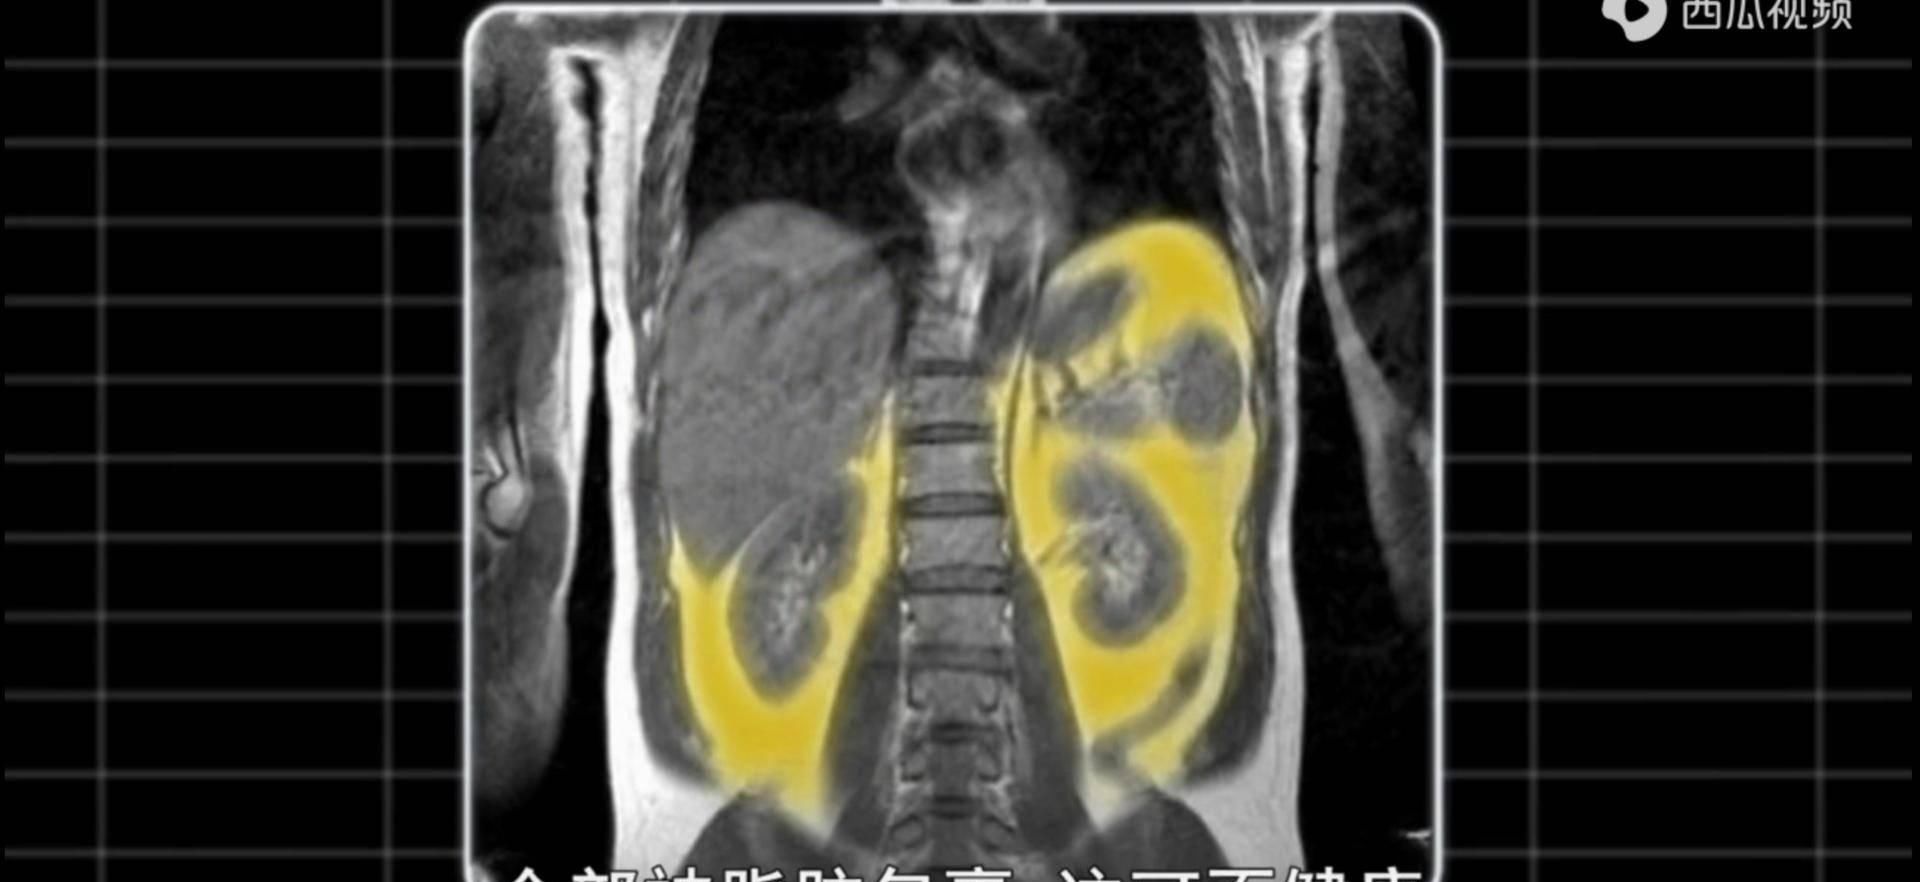

本片中第1位出镜的医学采访人员小迈。就是这样一个人。他没有双下巴、粗大腿,他的脂肪潜藏在身体内部,叫做内脏脂肪,比皮下脂肪更危险。

这种脂肪人眼是看不到的,需要用机器进行扫描。小迈去医院进行了检查,发现他的肾脏肝脏周围全被内脏脂肪包裹了。

这些内脏脂肪很有可能引发2型糖尿病和胰岛素抵抗。

内脏脂肪和一般的脂肪不同,它释放出的化学物质能够损坏心脏周围的动脉,从而导致心脏病。这些化学物质还会增加癌症风险。

位于肝脏附近的内脏脂肪释放出的化学物质很容易入侵肝脏,从而影响肝脏清除血液中胰岛素的能力,这就很有可能引发2型糖尿病。